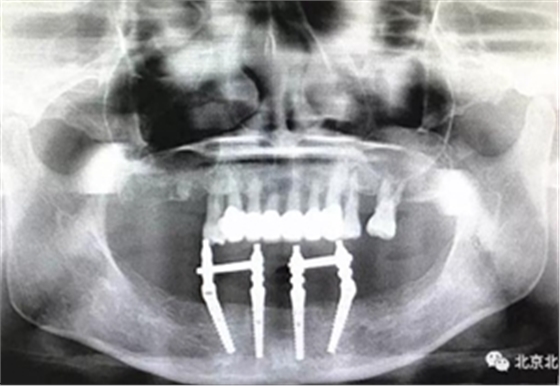

圖十五:術(shù)后即刻拍X片

圖十七:拍X片確認無誤差

圖二十一:半年后復(fù)查X片

圖二十二:2015年到2016年復(fù)查時X片 ,有圖有真相

沒有假貨,貨真價實,完成三年復(fù)查。

圖二十四:2017年11月復(fù)查時照片,植體很穩(wěn)定, 無骨吸收。